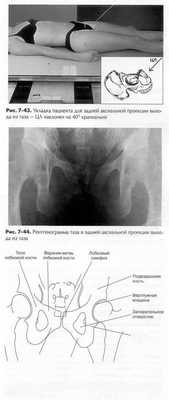

'ЯЯ ДВУХСТОРОННЯЯ ПРОЕКЦИЯ В ПОЛОЖЕНИИ ЛЯГУШКИ: ТЛЗ

Модифицированная по методу Кливза

Укладка пациента

Пациент лежит на спине, под его голову кладется подушка, руки пациента скрещены на груди.

Укладка снимаемой областиЩ

• Тело пациента выравнивают по центральной линии стола

и/или кассеты и по ЦЛ.

• Нет ротации таза (одинаковое расстояние от ВППО до стола).

• ЦЛ направлен на центр кассеты, на уровне головок бедрен

ных костей, верх кассеты расположен приблизительно на

уровне подвздошного гребня.

• Оба колена согнуты примерно на 90°, как показано на рис. 7-40.

• Подошвенные поверхности стоп пациента сведены вместе и

оба бедра отведены на 40-45° от вертикали (см. примечание

2). Бедра должны быть отведены на одинаковый угол, рота

ция таза отсутствует.

• Если необходимо, для стабилизации используйте опору под

каждую ногу.

Центральный луч

• ЦЛ перпендикулярен кассете, направлен на точку 7,5 см

ниже уровня ВППО (2,5 см выше лонного сочленения).

• ЦЛ направлен на центр кассеты.

• Минимальное РИП составляет 100 см.

Диафрагмирование.Диафрагмируйте по границам кассеты

с четырех сторон.

Малый Запирательное Головка

вертел отверстие бедренной кости

Рис. 7-42.Анатомическая схема таза в двухсторонней проекции в позиции лягушки

Дыхание.Пациент должен задержать дыхание во время экспозиции.

Примечание 1: эту проекцию часто выполняют при периодических исследованиях детей, поэтому важно правильно расположить гонадные экраны у пациентов обоего пола, при этом тазобедренные суставы не должны быть закрыты.

Примечание 2: отведение бедер на меньший угол, например только на 20-30° от вертикали, дает наименьшее укорочение шеек бедренных костей, но при таком положении укороченной выглядит вся проксимальная область бедренной кости, что может быть нежелательным.

Критерии оценки рентгенограммы Видимые анатомические структуры.• На одном снимке видны головки и шейки бедренных костей, вертлужная впадина и области вертелов.

Укладка.• Об отсутствии ротации свидетельствует симметричность тазовых костей, особенно крыльев подвздошной кости, запирательных отверстий и седалищных остей, если они видны. • Если оба бедра отведены правильно, то головки и шейки бедренных костей и большие и малые вертела должны быть симметричны. • Малые вертела, выступая за нижним или медиальным краем бедренной кости, должны быть одинаковы по размеру. • Большие вертела, главным образом, накладываются на шейки бедренных костей, которые выглядят укороченными (см. примечание 2).

Диафрагмирование и ЦЛ.• Тазовый пояс должен находиться в центре поля диафрагмирования по направлению справа налево, при этом средняя точка расположена примерно 2,5 см выше лобкового симфиза.

Параметры экспозиции.• Оптимальная экспозиция визуализирует контуры головки бедренной кости и вертлужную впадину через наложенные на них структуры таза, без переэкспонирования проксимального отдела бедренной кости. • Трабекулярная костей должна быть видна отчетливо, что указывает на отсутствие движения при экспозиции.